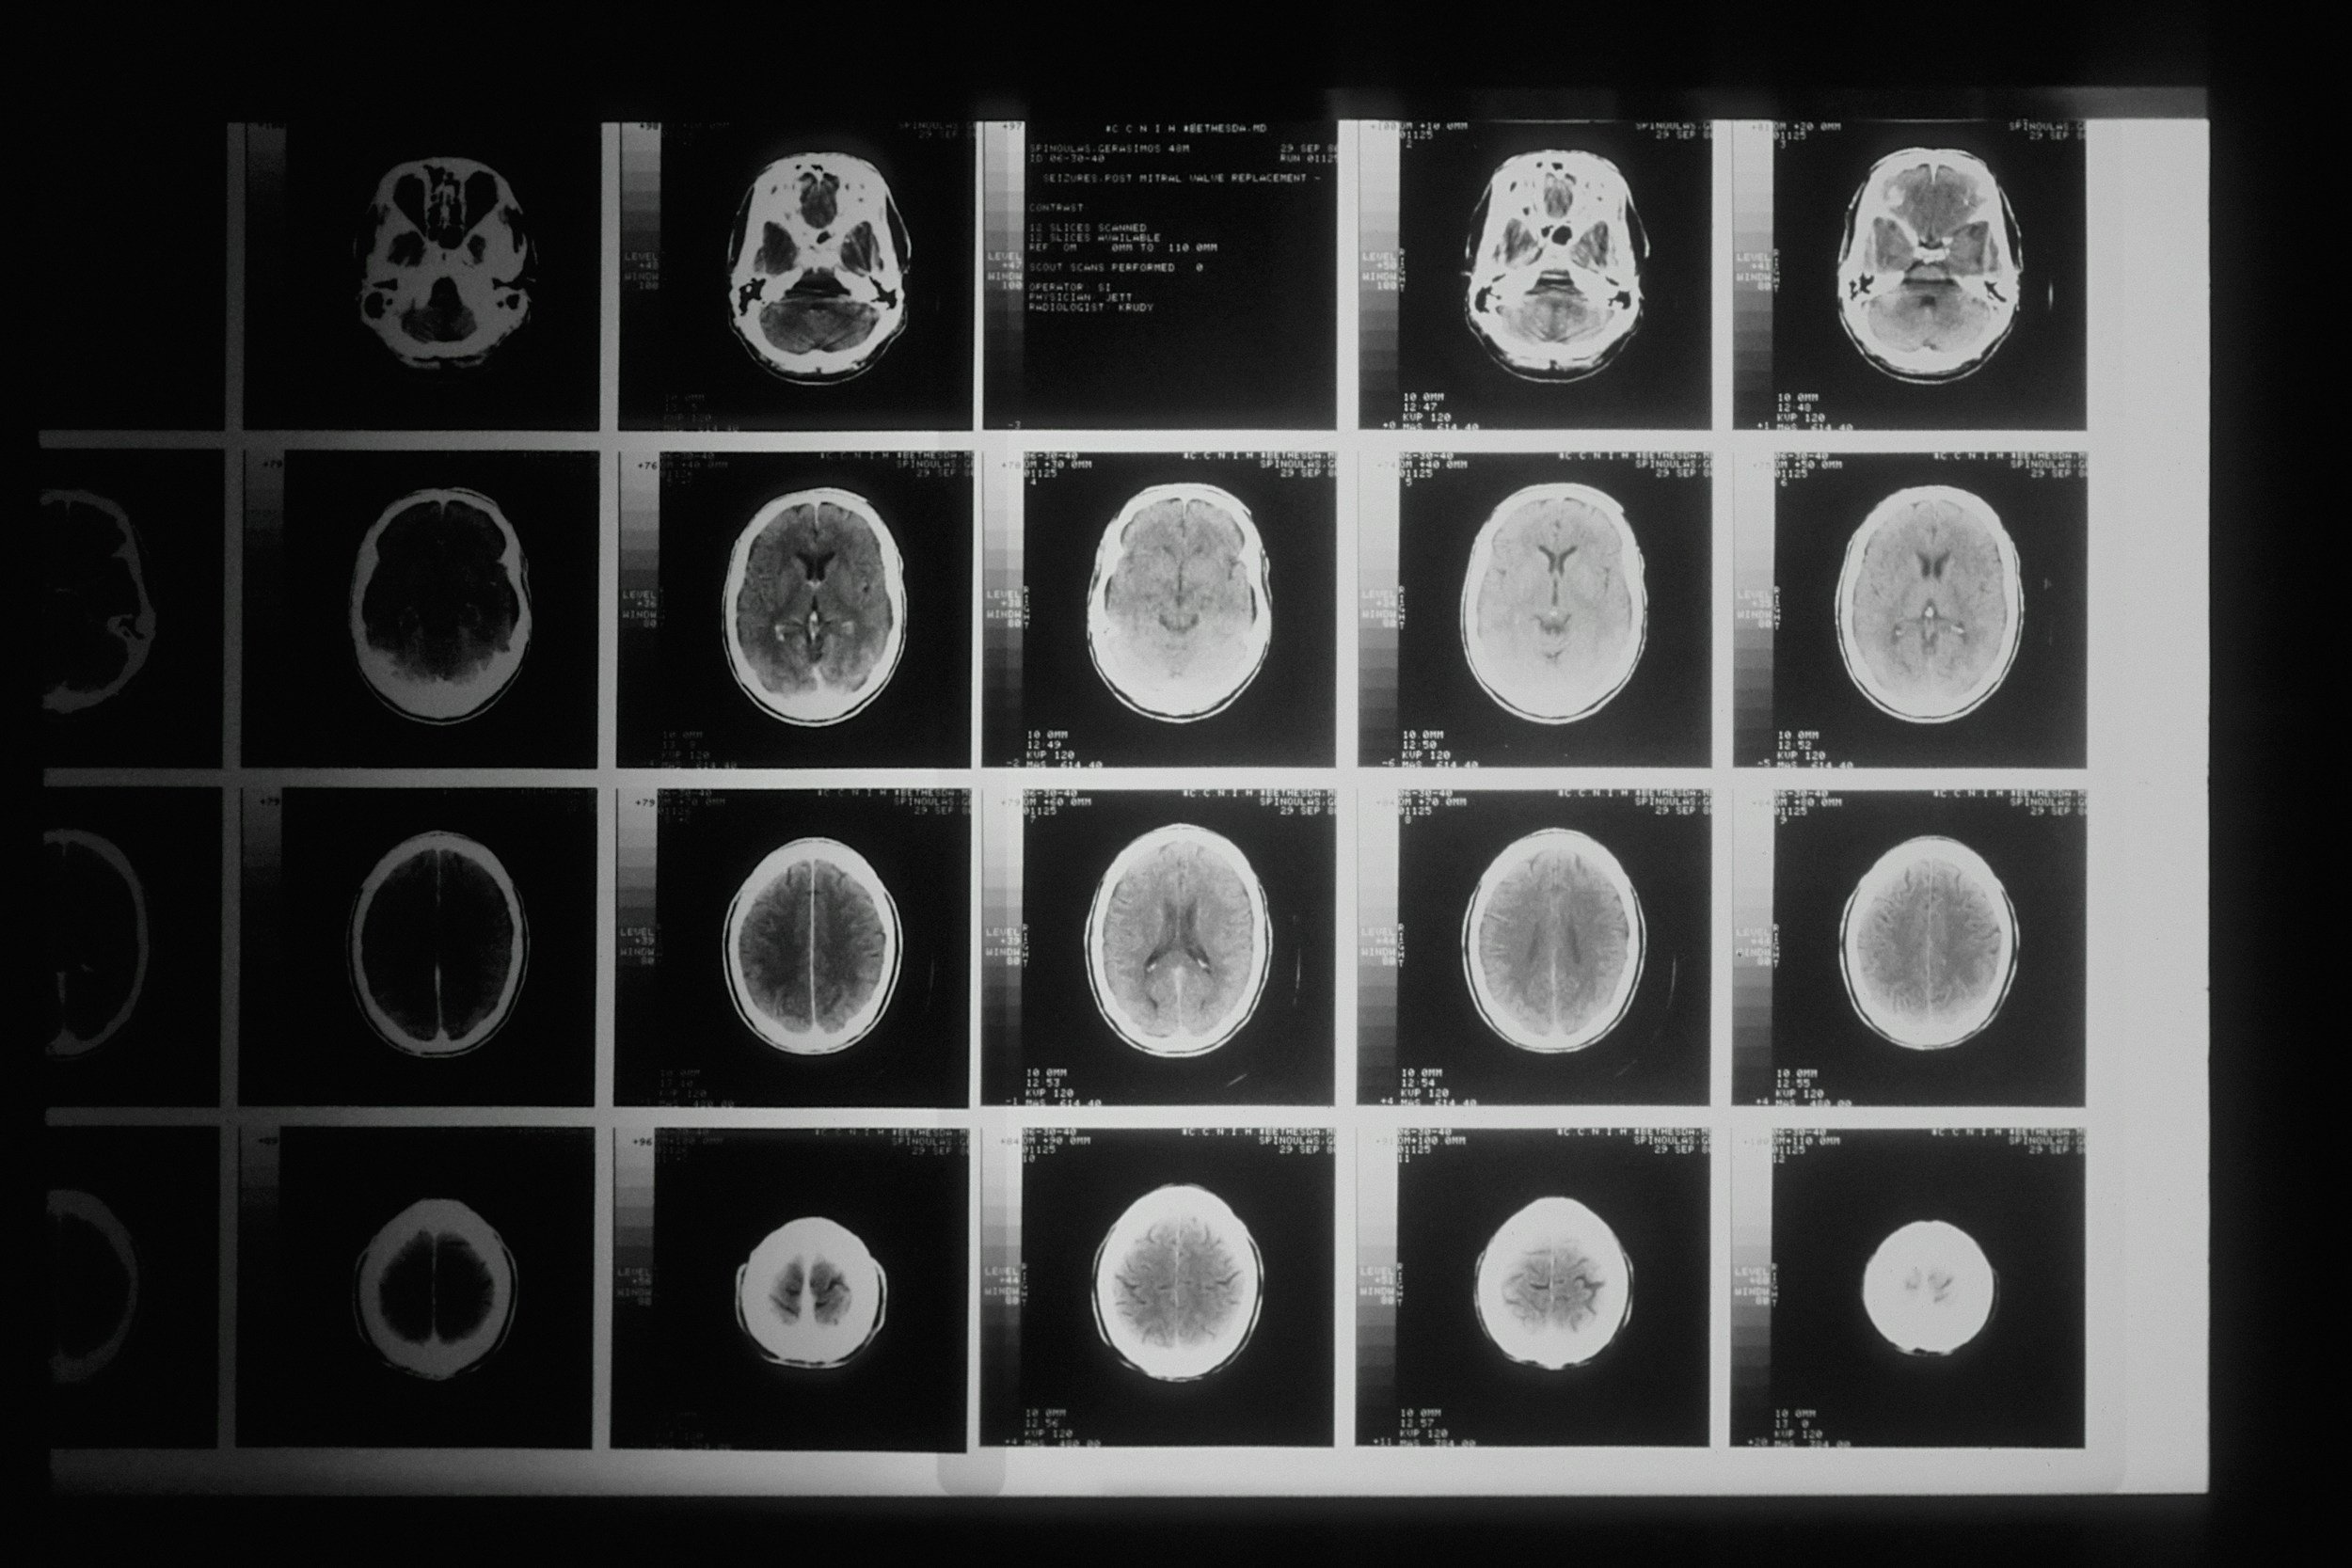

Scanner, IRM, résultats

Pour beaucoup de personnes en parcours de soin, l’examen médical n’est pas qu’une simple formalité technique. C’est un moment de vulnérabilité extrême. Entre l’attente dans la salle froide, le bruit imposant de l’IRM et l’appréhension des résultats, une forme d’anxiété de performance médicale s’installe. On a l'impression que notre corps passe un examen dont on redoute la sentence.

Face à la machine, le corps entre souvent en mode "survie". Le cœur s'accélère, la respiration devient haute et courte, et les pensées s'emballent. Cette réponse physiologique amplifie la sensation d'oppression, rendant l'examen encore plus difficile à supporter.